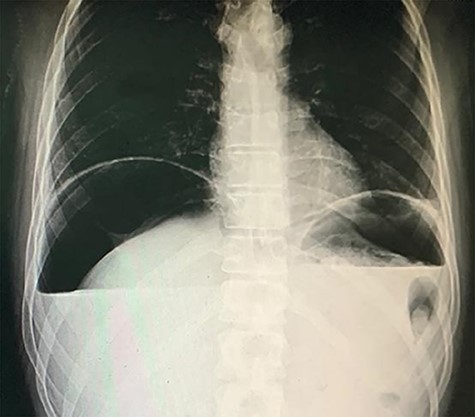

A 38-year-old male intravenous drug user presented to the emergency room with right iliac fossa pain of 3-hour duration. He had a previous surgical history of laparotomy and pan-proctocolectomy with ileoanal anastomosis indicated for his familial polyposis coli. Examination showed severe epigastric and right iliac fossa tenderness and rebound tenderness with a marked abdominal rigidity. Blood results showed blood urea nitrogen, 84; creatinine, 1.1; hematocrit, 63; K, 2.8; Na, 142; and total leukocytic count, 16.1. A chest X-ray was done and showed free air under the diaphragm (Fig. 1). An ultrasound showed a marked pelvic, peri splenic and perihepatic turbid collection.